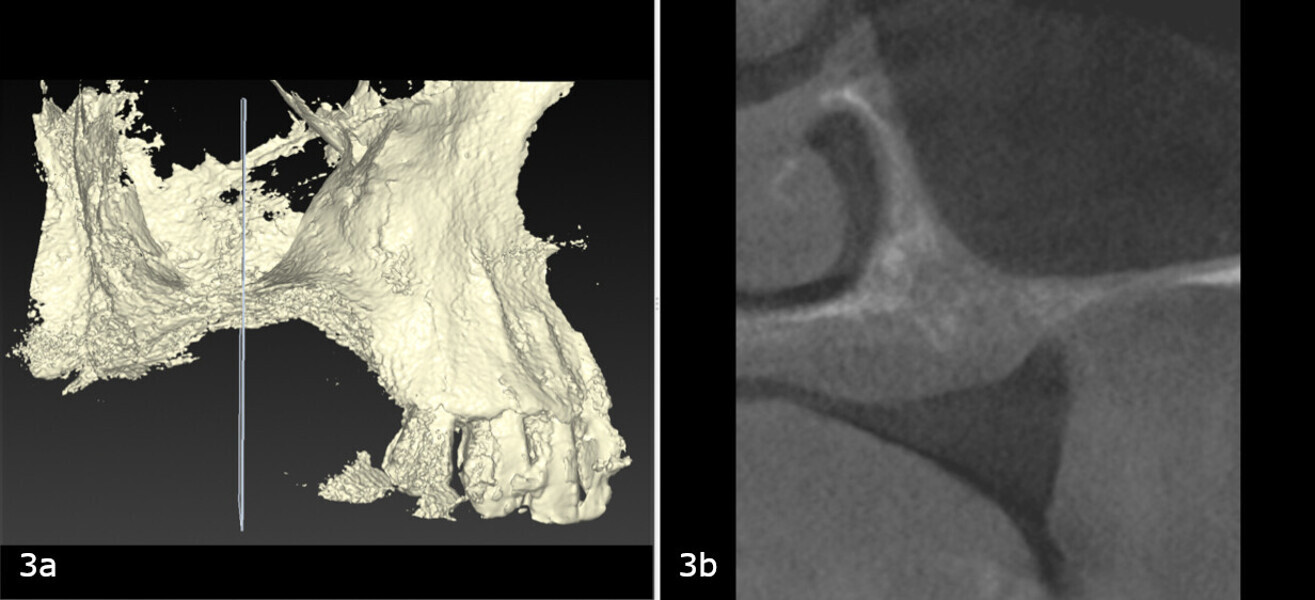

A 62-year-old female patient (ASA Class I), a non-smoker and with normal glucose levels, with previously treated periodontal disease presented for implant and prosthetic rehabilitation of the upper jaw (Fig. 1). Radiographic analysis, performed through a dental panoramic tomogram and CBCT scan, revealed the presence of a vertical bone defect in the right posterior sextant, due to the complete loss of the alveolar process (Figs. 2; 3a & b). The clinical examination showed the severity of the bone defect, which had resulted in an obvious volume deficiency in both the horizontal and vertical dimensions (Figs. 4 & 5).

The treatment plan was developed using a fully digital workflow. The DICOM files obtained from the preoperative CBCT scan were used to generate a 3D reconstruction of the maxilla, which allowed for the virtual design of the ideal bone volume for the placement of three implants in sites #15, 16 and 17 (Figs. 6a-d; 7a & b). Subsequently, the customised mesh corresponding to the increased volume in the patient’s maxilla was created virtually (Figs. 8a-f).